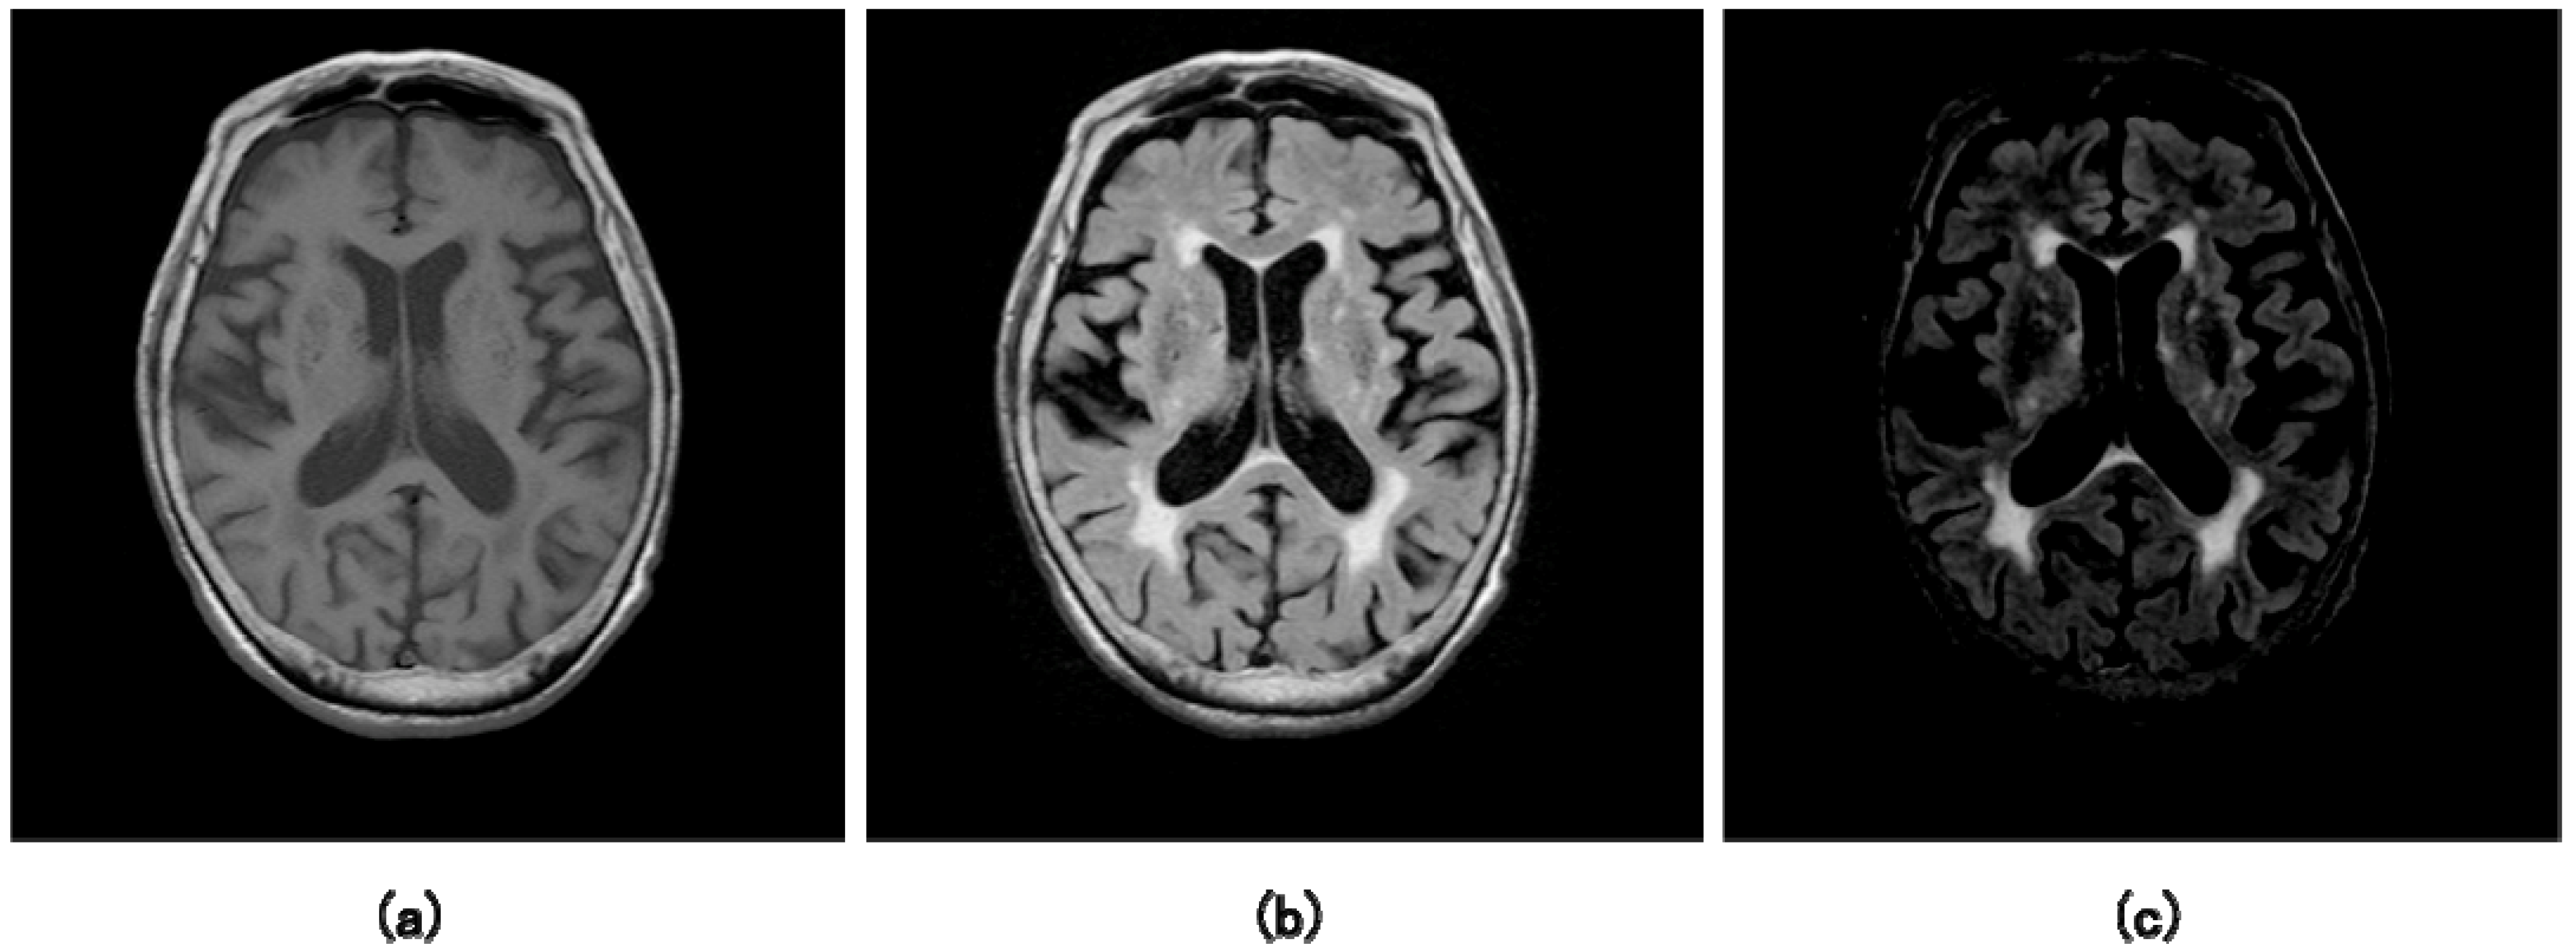

Subcortical vascular dementia (VaD) is a neurodegenerative vascular disorder that leads to a progressive decline in memory and cognitive functioning, and is considered the second most common cause of dementia in Japan. The prevalence of the VaD in people older than 70 years in Japan is around 27% including mix dementia of Alzheimer’s disease and VaD [67]. Ischemic lesions in VaD patients show hyperintense regions in the cerebral white matter, i.e., periventricular hyperintense (PVH) regions and white matter hyperintense (WMH) regions, on FLAIR images or T2-weighted images at MR imaging. It has been reported that the degree of the symptom of the VaD correlated with an area ratio of WMH region to the whole brain region (WMH region ratio) [68,69,70,71], which could provide diagnostic information for the treatment of VaD. Thus, it is very important to estimate the WMH region ratio for evaluating the degree of the VaD. Although neuroradiologists attempt to manually evaluate the WMH regions, it is very laborious and demanding in routine clinical practice. Therefore, investigators have reported CAD systems for detection of WMH including lacunar infarct using MR images [28,72,73,74,75,76]. Mohamed et al. [72] developed a segmentation method for white-matter lesions including VaD, multiple sclerosis, and lacunar infarcts based on a modified k-mean-neighbor method using three-dimensional (3D) MR images. Anbeek et al. [73] presented a method for automated segmentation of WMHs in MR images by using a k-nearest neighbor method, which builds a feature space from voxel intensity features and spatial information. Admiraal-Behloul et al. [74] proposed a automatic segmentation method of WMHs based on a fuzzy C-mean algorithm using three different MR images: proton density, T2-weighted, and FLAIR images. Uchiyama et al. [75] developed a computerized scheme for detection of lacunar infarct by using a rule-based method and an SVM. Their method detected 96.8% of lacunar infarct with 0.76 false positives. Zhiqiang et al. [76] suggested an approach for segmentation of white-matter lesions related to cerebrovascular disease based on a SVM on a 3D MR image. On the other hand, for assisting neuroradiologists in the diagnosis of VaD, Yamashita et al. [28] developed an automated method for detecting and segmenting WMH regions based on conventional MR images (T1-weighted, T2-weighted, and FLAIR images). Their method attained a sensitivity of 90% with 4.0 false-positives per slice in detection of WMH regions. Table 2 shows a comparison of methods and performance of CAD systems for segmentation of WMH using MR images. This table does not include the results of Mohamed et al., Uchiyama et al., and Zhiqiang et al., because they did not explicitly state the similarity index in their papers. According to Table 2, the sensitivities and similarity indices were higher than 90% and 74%, respectively. The researchers of CAD systems for detection of WMHs focus on segmentation accuracy, because the neuroradiologists should measure the WMH areas in MR images for diagnosis and follow-up of patients. In a method of Yamashita et al. [28], many false-positives were removed based on the outputs of four ANNs, which were considered the possibility of the WMH regions. Figure 12 shows the illustrations of (a) an original T1-weighted image, (b) an original FLAIR image with hyperintense regions, (c) a FLAIR-T1 subtraction image. As shown in Figure 12, a majority of WMH regions are in the periventricular region, which was divided into the anterior horn, posterior horn, and the periventricular body [77]. The left and right horns were located about 45°, 135°, 225°, and 315° from the centroid of a brain. Therefore, each brain was divided into four quarters (90°) based on this clinical evidence. Four ANNs were constructed for four divided brain regions. Input features for the ANN were mean, maximum, and minimum pixel values of a candidate in T1-weighted, T2-weighted, FLAIR images, and the FLAIR-T1 subtraction images, effective diameter, circularity, and the distance between a candidate and the centroid of a brain region.

Figure 12.

Illustrations of (a) an original T1-weighted image, (b) an original fluid-attenuated inversion-recovery (FLAIR) image with hyperintense regions, (c) a subtraction image between the FLAIR image and T1-weighted image [28].